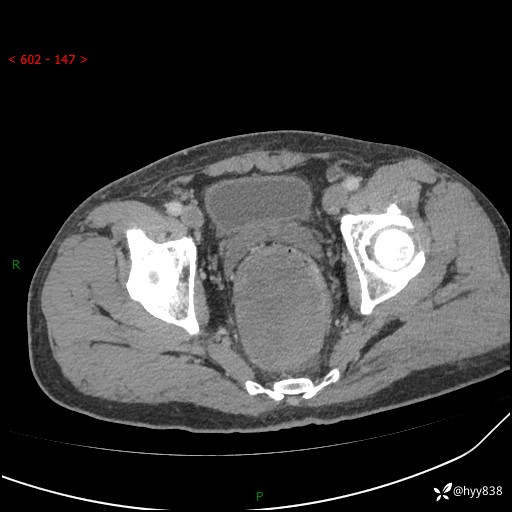

盆腔CT平扫+增强